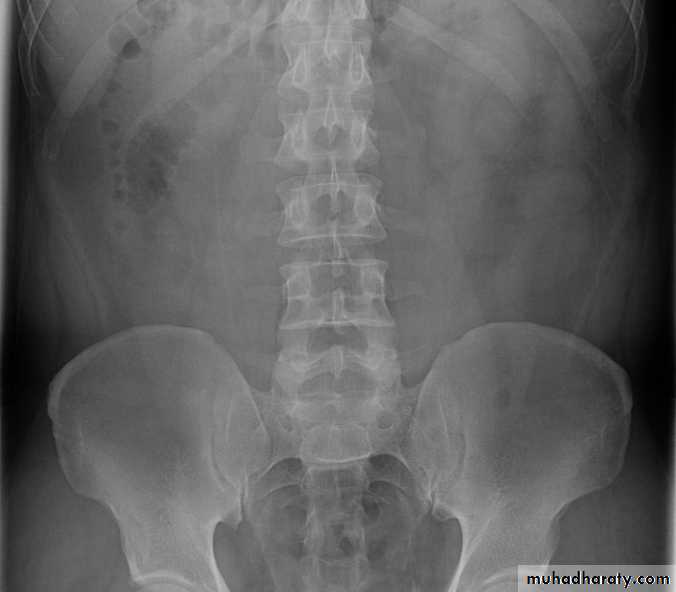

-Over 90% of calculi are radiopaque on plain films and virtually all on CT as very sensitive for detection of calculi, even those that appear radiolucent on plain film.-Most of these stones are a mixture of calcium oxalate and phosphate.

-Only pure uric acid and xanthine stones are radiolucent on plain x-ray but CAN be identified by CT or US, uric acid stones are associated with increased uric acid excretion in urine as in gout.

-Principal feature is dilatation of the pelvicalyceal system and ureter.

• The dilatation is down to the level of pathology

The prime objective of imaging is to determine the level and the cause of obstruction.